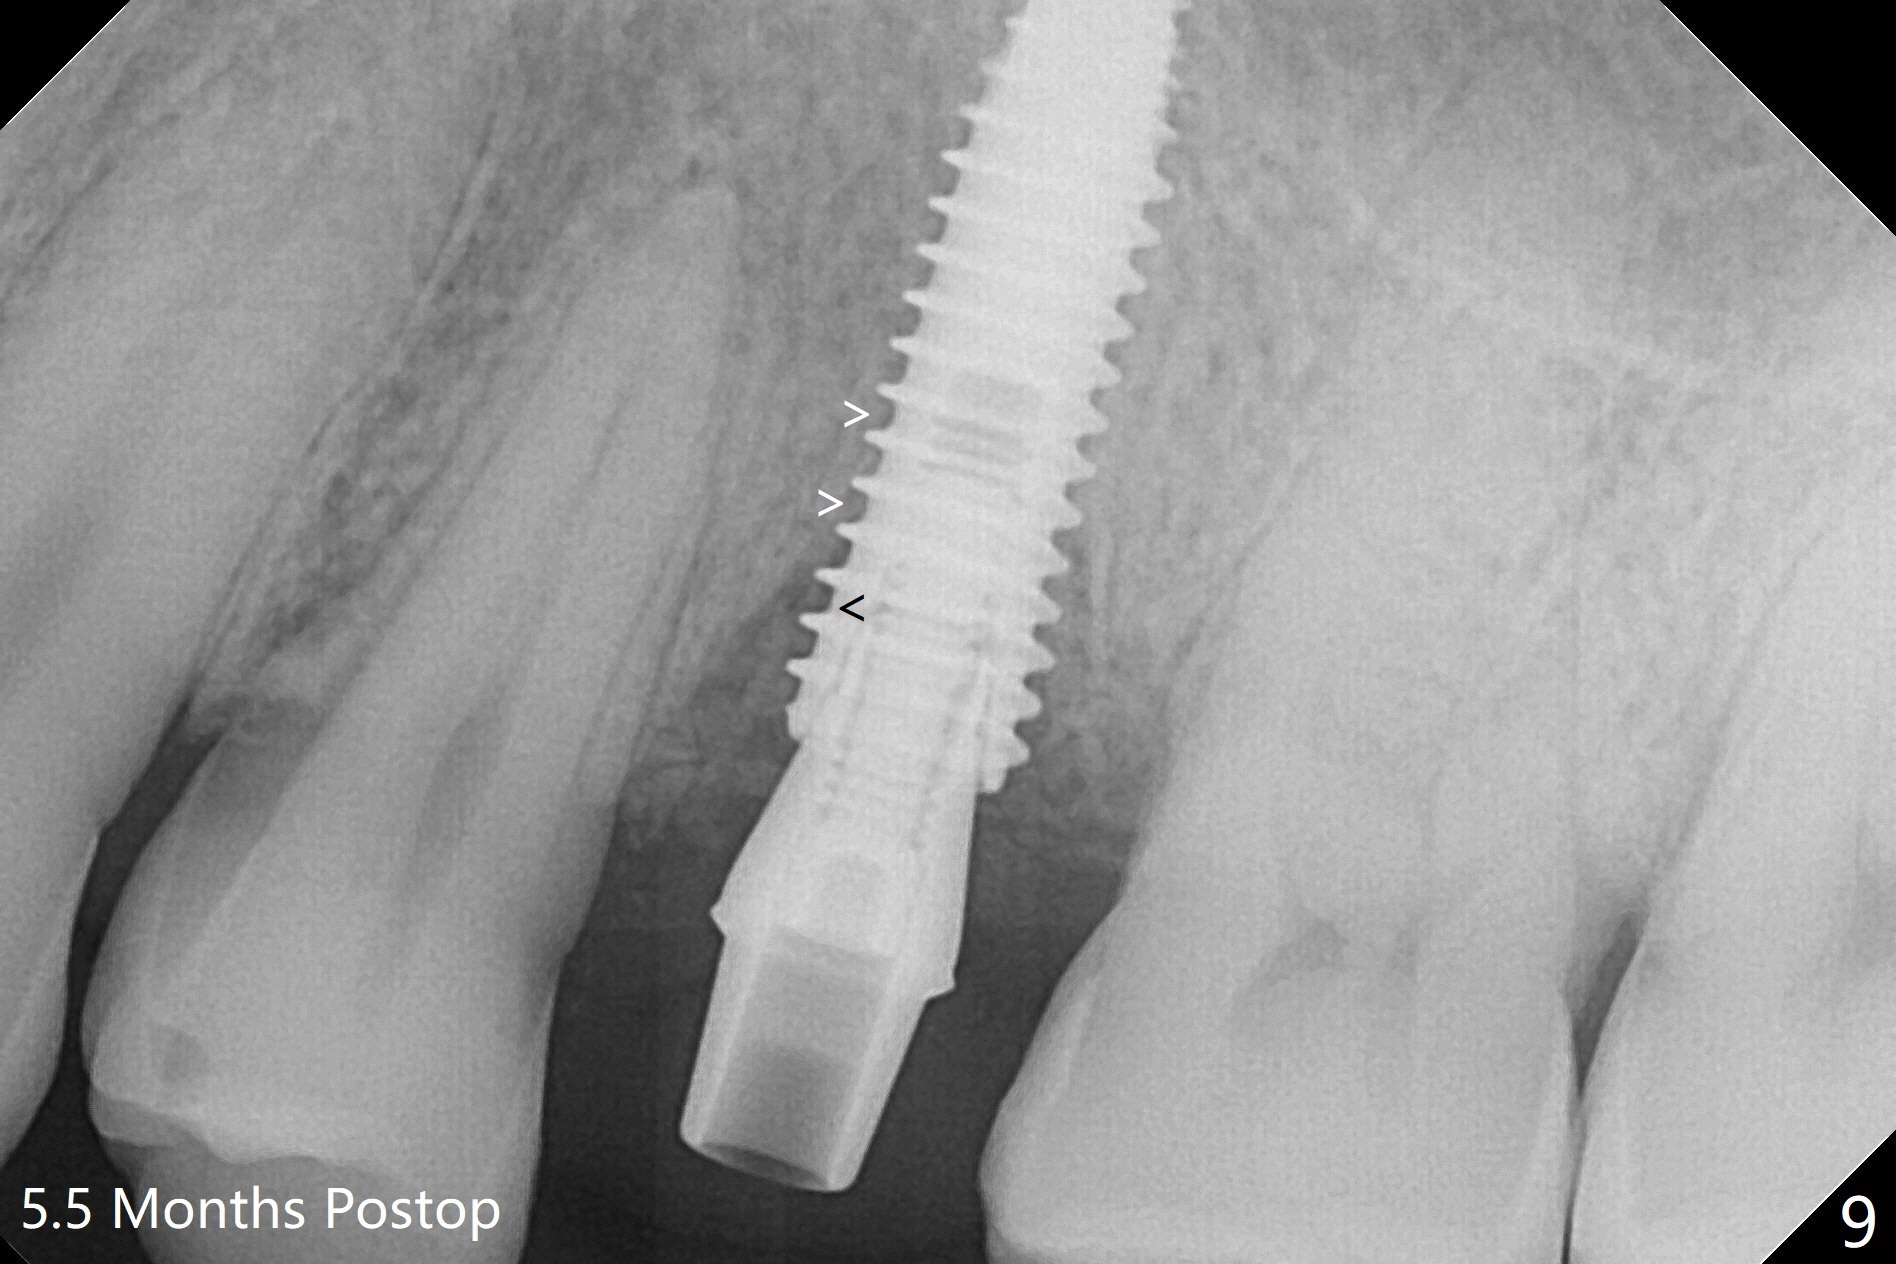

DIO lab refuses fabricating guide because of the large socket and recommends extraction and socket preservation at #13. Due to short apical bone (Fig.5,7), a long dummy implant (3.8x15 mm) is placed with periimplant space immediately post extraction (Fig.1 *). The final implant is larger (4.5x15 mm) with simultaneous sinus lift and periimplant bone graft (Fig.2,6,8 *). To repair the palatal crest defect (Fig.3 *) associated with tooth fracture (Fig.5 white dashed line), the implant is not placed too palatal with sufficient amount of the bone graft (Fig.4,6 *). The native bone (higher in bone density, Fig.9 white arrowheads, as compared to black one (for bone graft)) appears to have grown into the space between implant threads 5.5 months postop. The permanent crown/abutment is loose 1 year 9 months post cementation; after proximal reduction (Fig.10 arrowheads), the abutment is reseated completely. Pick up impression is taken and a healing abutment is placed. A few days later, the crown and abutment (separate) are seated passively; the abutment screw is retightened; the crown is re-cemented. The crown and abutment is removed for residual cement removal (Fig.11). Since there is mild buccal plate atrophy (Fig.11 B), the crown has a buccal lip (Fig.12 B) to prevent food impaction. The lip makes it difficult to remove residual cement intraorally. Therefore an access hole is necessary (Fig.13).